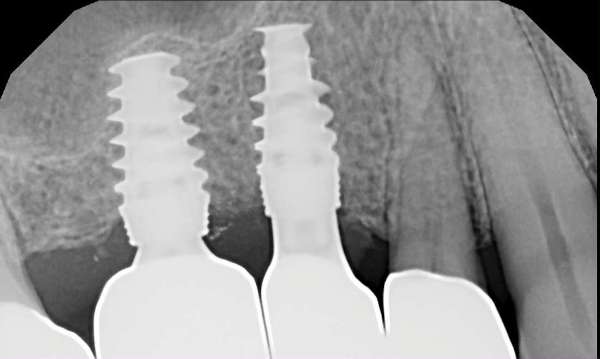

Anchor tooth for the patient's bridge failed and had to be extracted. Patient had two implants placed rather than replacing with a longer-spanning bridge.